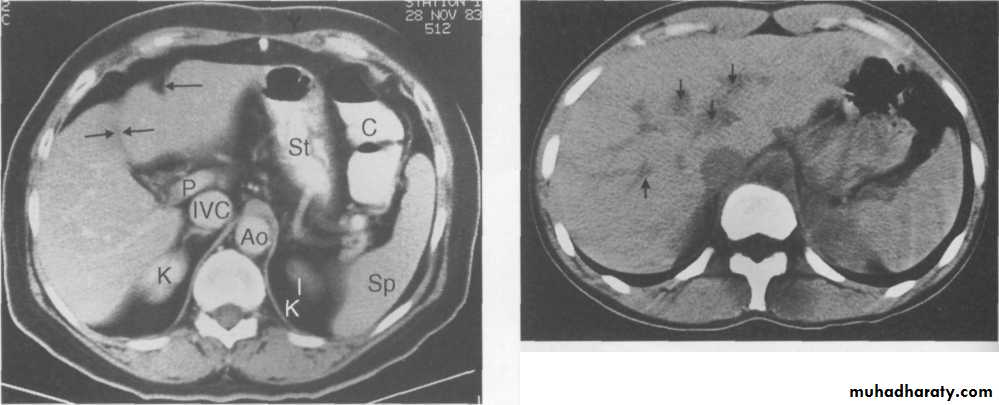

CT.scan

CT scan showing unopacified hepatic veins (arrows) which should not be confused with metastases.

CT Scans

Accurate in localizing the site of liver injury and any associated injuries

Used to monitor healing

CT criteria for staging liver trauma uses AAST liver injury scaleGrades 1-6